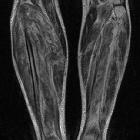

Hypovolemic

shock with subtle imaging signs: systemic capillary leak syndrome. Coronal (a,b) and axial (c) T2-weighted images showed hyperintense oedematous muscle swelling of both calves, particularly severe on the right side and mostly affecting the gastrocnemius and soleus muscles.

shock with subtle imaging signs: systemic capillary leak syndrome. Axial fat-suppressed T2-weighted images (d,e) better showed intramuscular oedematous changes, with associated fluid-like epimysial, perimysial and fascial effusions, causing swelling particularly severe in the right calf.